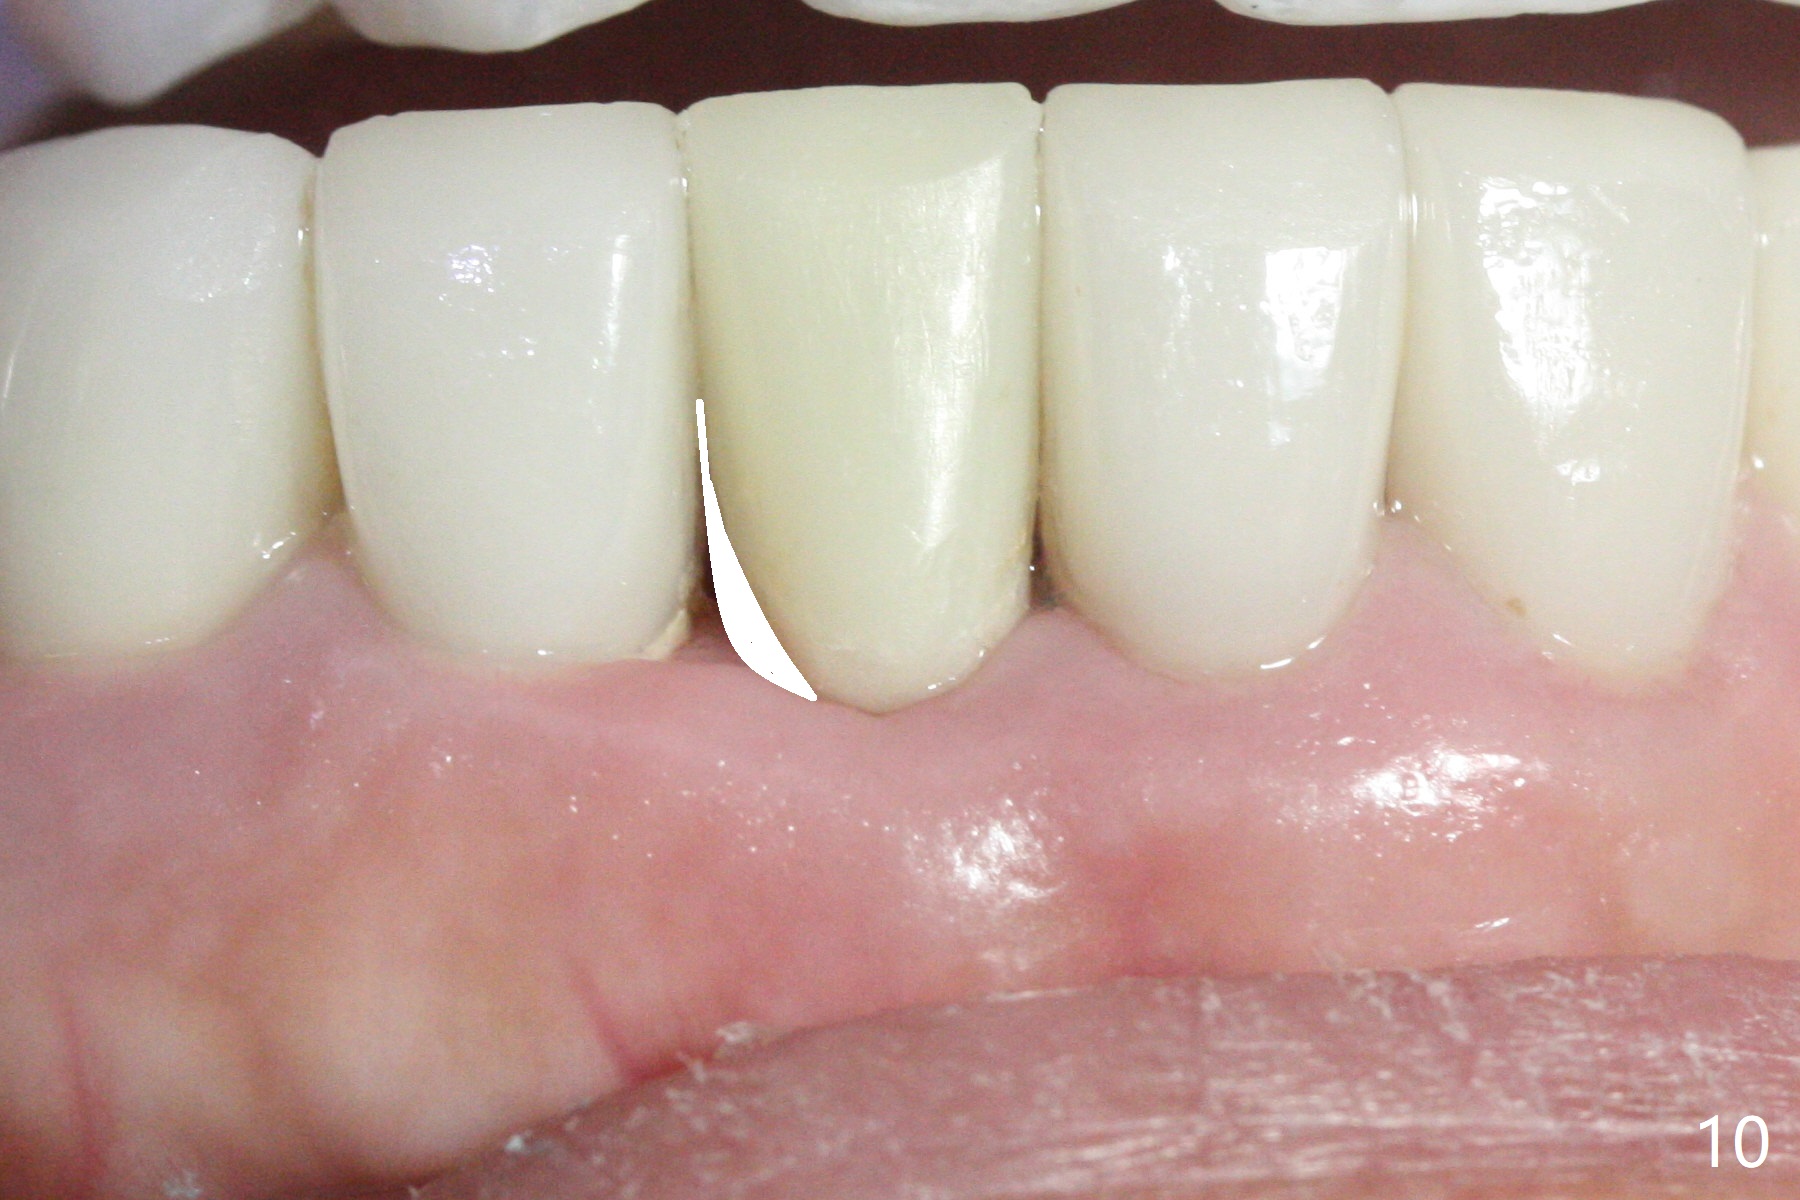

A drawback of implant planning at #25 is not to use a preop PA (Fig.1 (^ fracture line)). The initial trajectory seems to be alright (Fig.2), but a 2.5x14(2) mm implant placed is close to the tooth #26 (Fig.3). In fact the affected tooth is deviated distal; osteotomy should be initiated in the mesial slope of the socket (Fig.4 red line). The final trajectory appears to be perfect (Fig.5). Furthermore the 1st intraop PA should be analyzed carefully (Fig.6). A new osteotomy should be established mesial or the existing one should be moved mesial with Lindamann bur (Fig.7). The distal implant placement may be related to more bone loss in the distal crest 3.5 months postop (Fig.8) and more severe distal papillary recession (Fig.9 *). The bone density increases at the levels of the non-thread and thread portions of the implant (in the original socket) nearly 10 months post cementation (Fig.11 *, <). There is no bone loss 16 months post cementation (Fig.12).